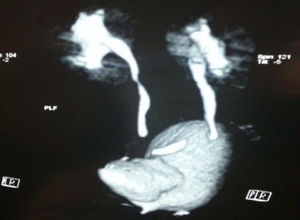

El 29.09.09 se realiza cistograma miccional donde se observa vejiga septada que comunica directamente con la uretra y reflujo vesicoureteral derecho grado iii (GIII) (fig. 1).

Por los hallazgos en estudio de imagen previo, se solicita uro-TAC en la cual se observa divertículo vesical paraureteral derecho y reflujo vesicoureteral GII (figs. 2 y 3); el paciente durante el estudio y posterior al mismo se encontró asintomático.